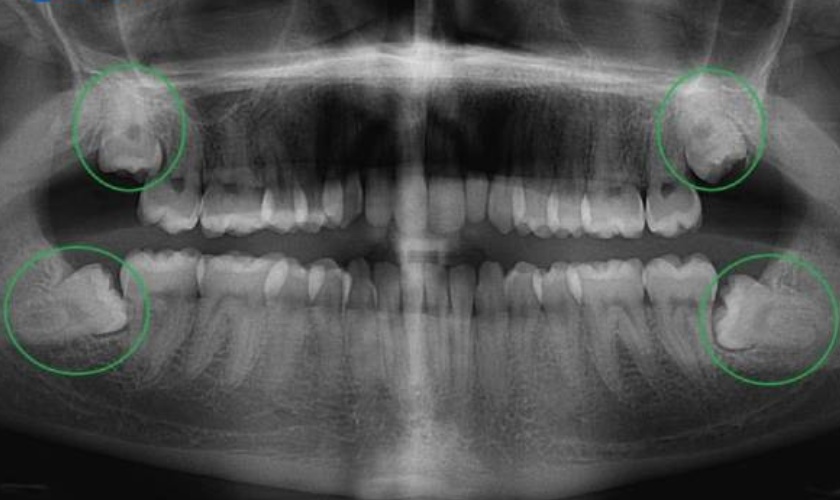

Tuy nhiên, không phải ai cũng mọc đầy đủ 4 chiếc răng khôn. Có người chỉ mọc 1, 2 hoặc 3 răng khôn. Hoặc cũng có trường hợp không mọc chiếc răng khôn nào. Bên cạnh đó, răng khôn mọc khi xương hàm đã phát triển hoàn thiện, mô nướu dày dặn, do đó có thể phát sinh thành hai tình huống:

- Răng khôn mọc thẳng, cân đối như răng bình thường nếu như cung hàm vẫn còn đủ chỗ trống. Trường hợp này răng khôn sẽ không gây bất kỳ biến chứng nào miễn là chúng khỏe mạnh, không mắc phải các bệnh lý răng miệng.

- Răng khôn mọc lệch, mọc ngầm,… do cung hàm không còn đủ chỗ trống. Trường hợp này được đánh giá là khá nguy hiểm bởi nó có thể gây nên nhiều biến chứng, ảnh hưởng đến sức khỏe răng miệng và sức khỏe toàn thân.